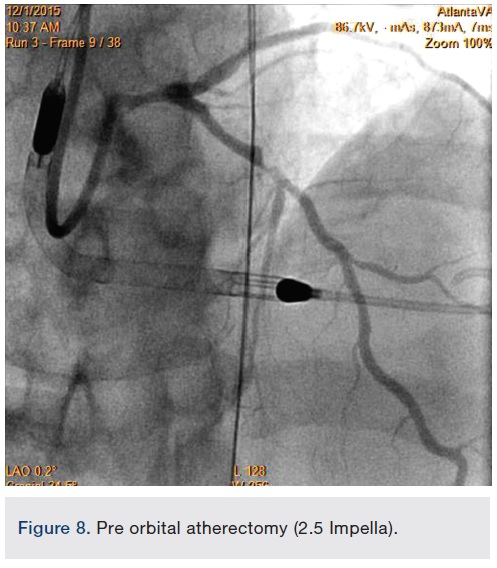

Following successful completion of the peripheral phase, it was felt that a 4-week period was necessary for the iliac stent to heal somewhat (especially since we planned to place a 14 French Cook sheath through it). We then moved on to the coronary phase of this procedure. Bilateral groins and the right wrist were prepared and draped in the usual sterile fashion. Using micropuncture technique with fluoroscopic verification of needle entry into the left CFA at the upper quadrant of the femoral head, a 6 French sheath was placed in the left CFA. The existing left femoral arterial sheath was removed, and the arteriotomy was pre-closed with a single Perclose device (Abbott Vascular). The arteriotomy was then serially dilated with 10, 12 and 14 French dilators, and a 14 French, 30 cm Cook sheath was placed successfully in the left common femoral artery. Following therapeutic anticoagulation with intravenous heparin, a regular J-wire and a 6 French pigtail catheter were used to cross the aortic valve, and the catheter was used to exchange the J wire for the 0.018-inch Platinum Plus wire (Boston Scientific). The Impella CP (3.5) percutaneous left ventricular assist device (LVAD) (Abiomed) was inserted into the left ventricle over the Platinum Plus wire (Figure 8). The Impella was then activated and good flows were verified. Right radial artery access was obtained and a PB 3.0 7.5 French sheathless guide system (Asahi Intecc) was used to engage the left main coronary artery. The LAD was wired uneventfully using a Runthrough wire (Terumo) via a 1.25 x 6 mm over-the-wire (OTW) Sprinter balloon (Medtronic). This was then exchanged for a Viper wire (CSI). Orbital atherectomy of the proximal LAD lesion was performed with excellent results (80,000 rpm x 4 passes, 120,000 rpm x 2 passes) (Figure 9). The LAD wire was then exchanged for a Runthrough wire and the left circumflex (LCX) was wired with a BMW wire. Following plaque modification with orbital atherectomy, predilation of LAD was performed with 3.0 x 20 mm Chocolate Balloon (QT Vascular Ltd) (15 atmospheres x 60 seconds and 15 atmospheres x 30 seconds) (Figure 10) with an excellent result and no dissection (Figure 11). A 3.5 x 38 mm Promus stent (Boston Scientific) (14 atmospheres x 30 seconds) was placed from the left main into the proximal LAD lesion ensuring adequate coverage. The jailed LCX wire was recovered and re-placed in the LCX through the struts of the newly placed LM-LAD stent (Figure 12). Predilation of the LCX ostium was performed with a 2.5 x 8 mm Glider balloon (QT Vascular Ltd) (14 atmospheres x 25 seconds). The mid LAD was stented (ensuring overlap with proximal stent) with 3.0 x 16 mm Promus stent (16 atmospheres x 25 seconds). A final kissing balloon inflation of the LAD/LCX with an NC Sprinter 2.5 x15 mm balloon (Medtronic) into the LCX and a NC Sprinter 3.5 x12 mm balloon into the LAD was performed, with up to 16 atmospheres x 20 seconds on both (Figure 13). Final IVUS of the LM and LAD stent revealed excellent results and the LCX ostium looked excellent as well (Figures 14-16).